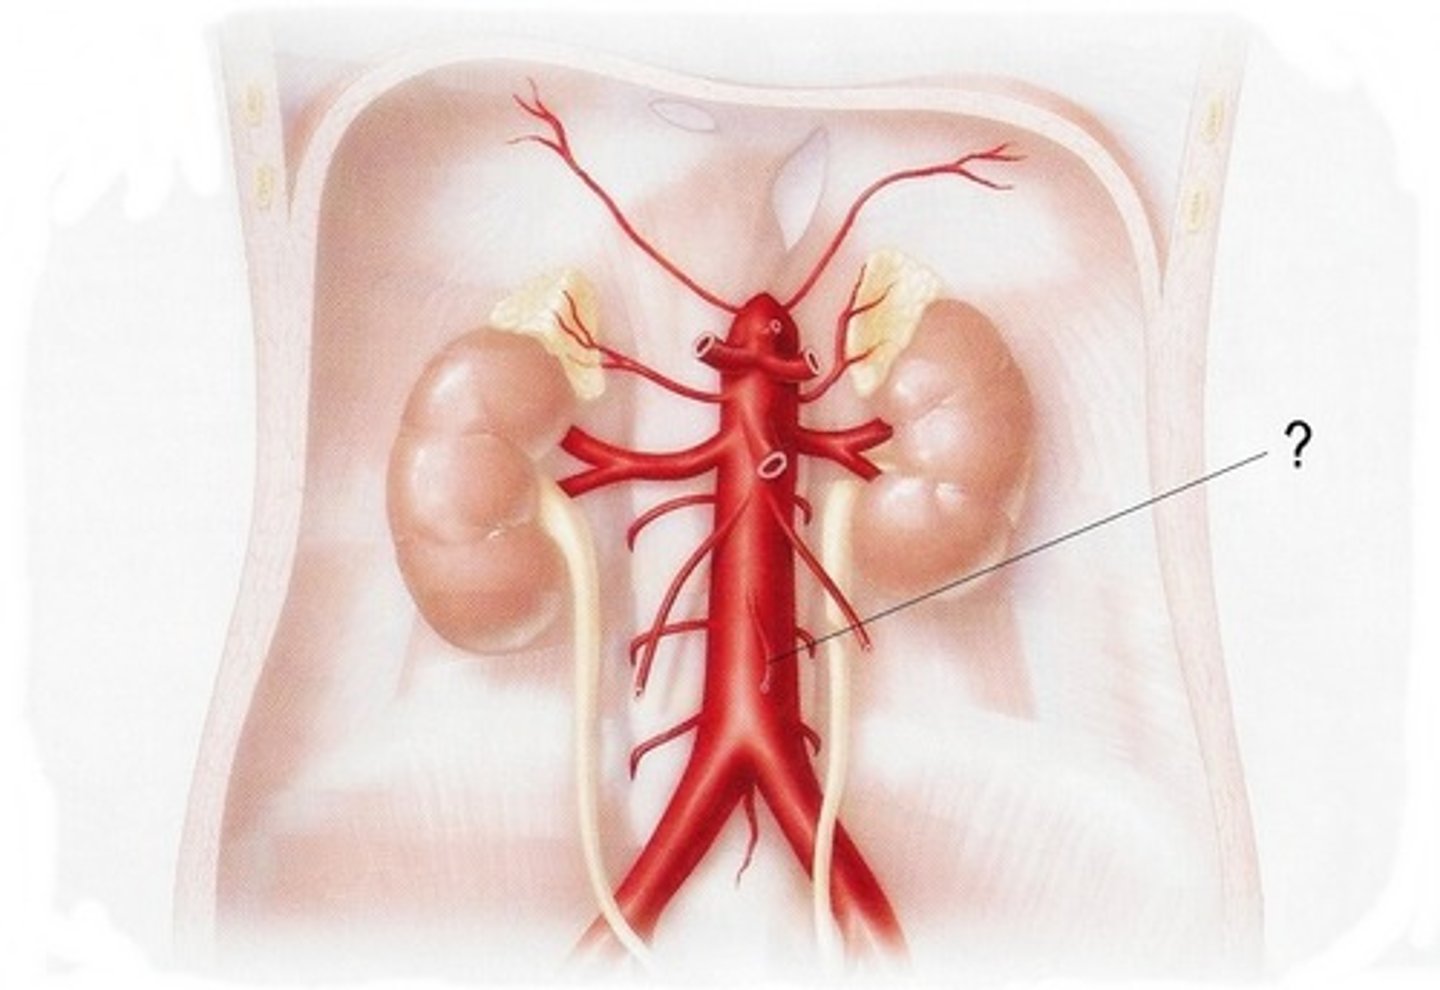

renal artery

serves the kidneys

gonadal artery

serves reproductive organs